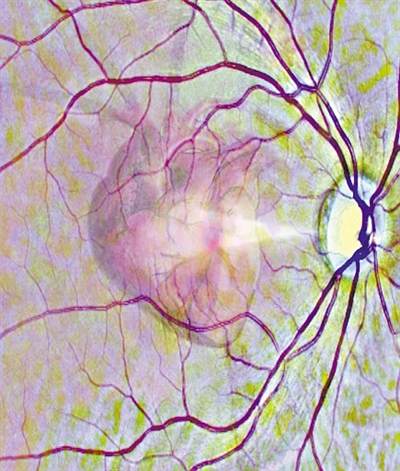

通過視網膜掃描來了解心臟健康狀況(示意圖)。圖片來源:利茲大學官網

視網膜微小血管的變化是更廣泛的血管疾病,包括心臟問題的指標。在英國利茲大學領導的這項研究中,研究人員利用深度學習技術訓練AI系統自動讀取視網膜掃描數據,并識別那些在接下來的一年中可能會得心臟病的人。深度學習是一系列復雜的算法,使計算機能夠識別數據中的模式并作出預測。

英國生物銀行為這項研究提供了數據。在深度學習過程中,AI系統分析了5000多人的視網膜掃描和心臟掃描數據。AI系統確定了視網膜病變與患者心臟變化之間的關聯。

一旦學習了圖像模式,AI系統就可以僅通過視網膜掃描來估計左心室(心臟的四個腔室之一)的大小和泵送效率。心室擴大與心臟病風險增高有關。借助有關左心室估測大小及其泵送效率的信息以及有關患者年齡、性別等基本人口統計數據,AI系統可預測他們在接下來的12個月內心臟病發作的風險。